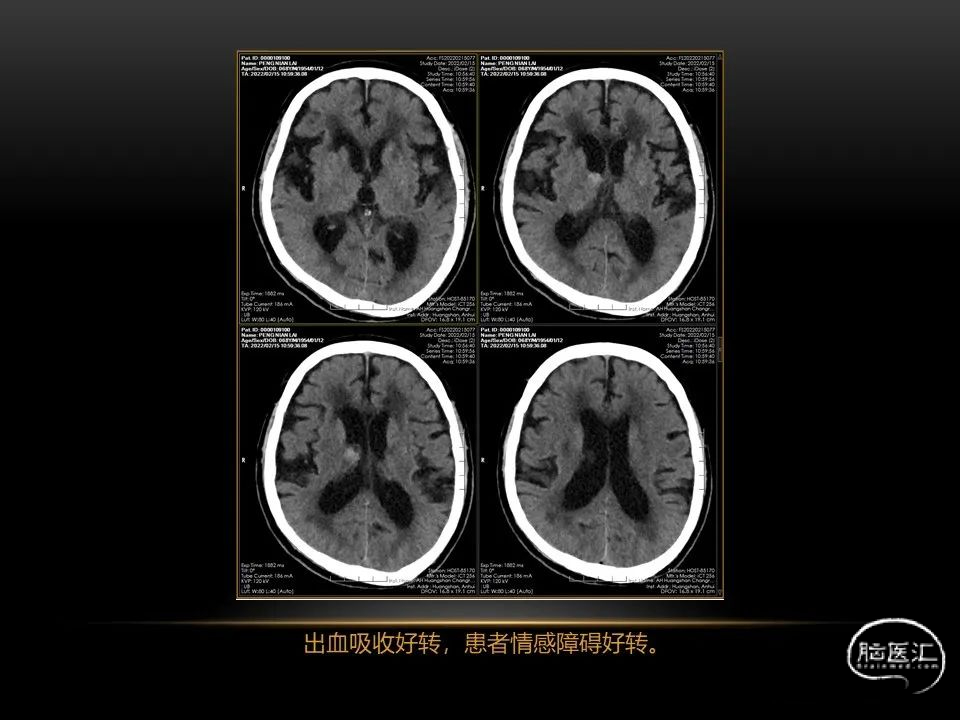

自发性脑出血临床上很常见,不同原因有特征性的出血部位。例如:基底节出血和丘脑出血大多是高血压性脑出血;脑叶出血,特别是多次复发的脑叶出血多见于老年人的脑血管淀粉样变。

自发性脑出血不仅仅累及内囊后肢才会出现偏瘫及偏身感觉障碍,病变累及大脑脚或辐射冠同样有可能有类似症状和体征。内囊、辐射冠、大脑脚等结构之间是延续的,只是不同区域不同名称而已。定位诊断需要对解剖结构概念清晰,读片准确辨认,灵活掌握。